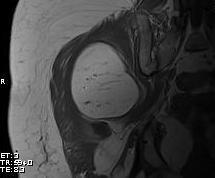

MRI

Same signal intensity as surrounding fat